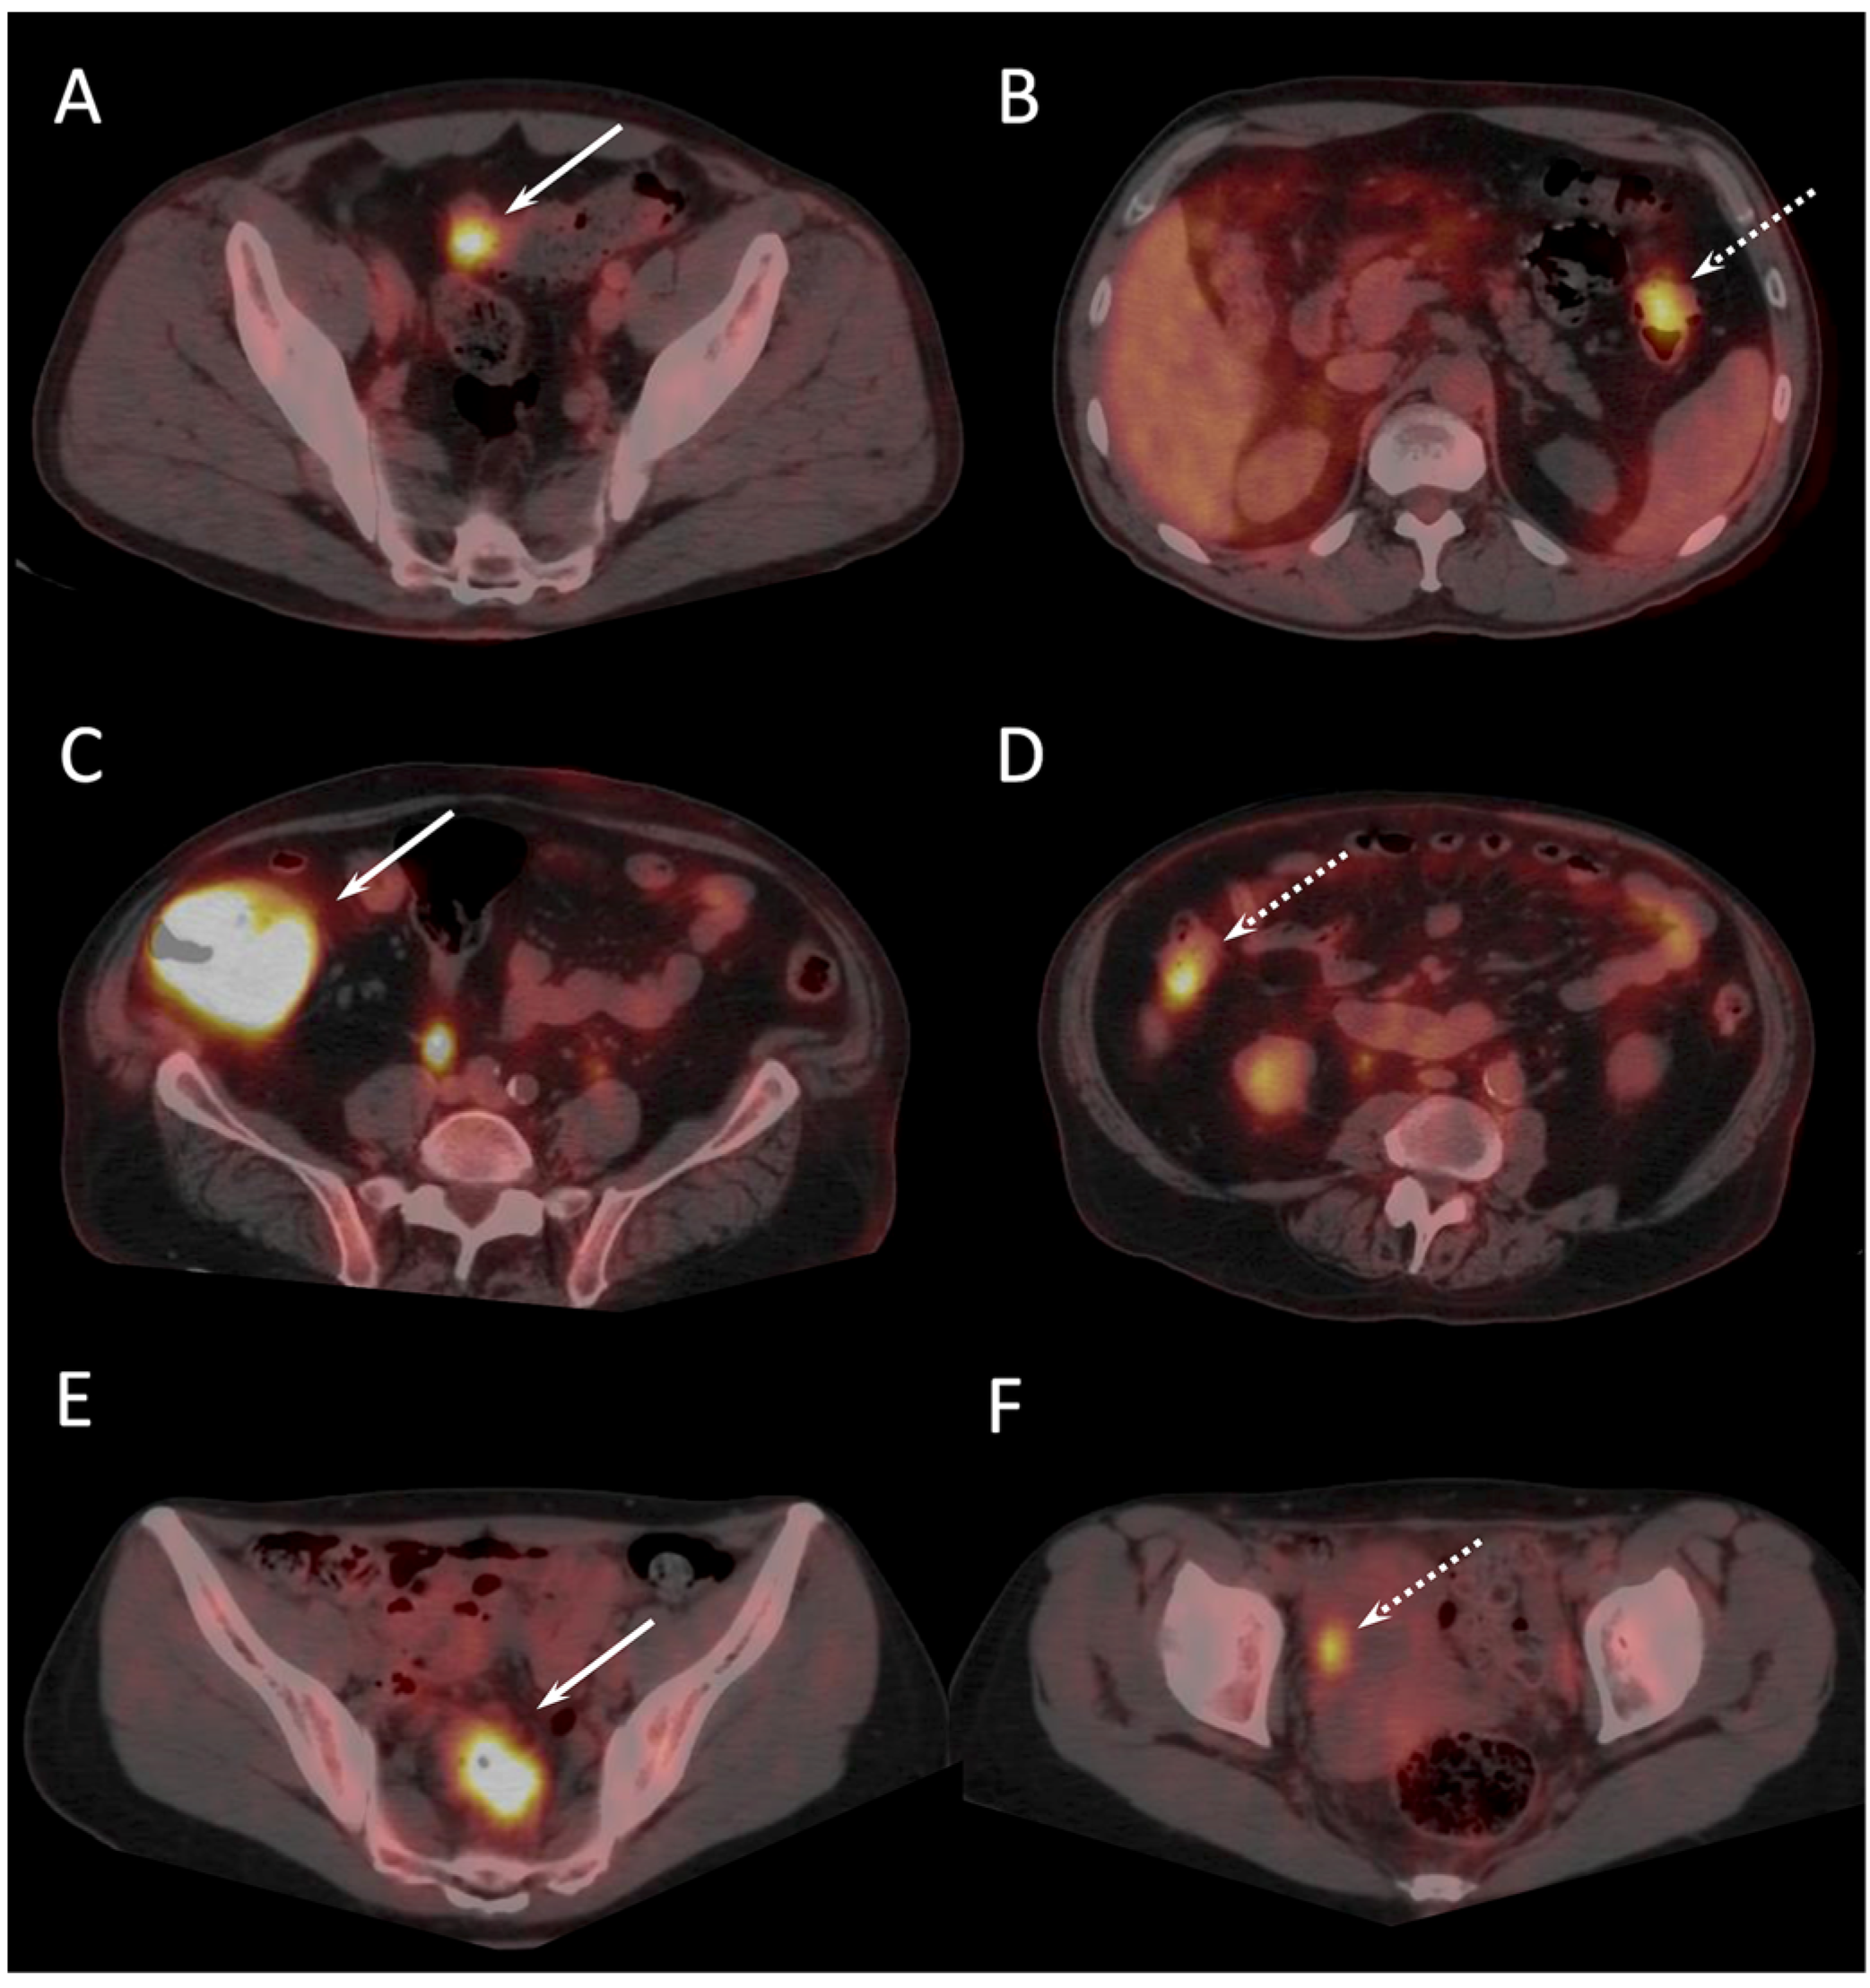

The mean delay between 18F-FDG PET/CT and CI was 29.8 ± 12.9 days (range, 7–53 days), and between 18F-FDG PET/CT and surgery was 5 ± 4 days (range, 1–23 days). Thirty-six out of forty-eight included patients who underwent dual-time-point PET/CT images (standard whole-body followed by delayed abdominal and pelvic scans). PET/CT analysis of the large bowel was not feasible in two diabetic patients due to diffuse intestinal 18F-FDG uptake related to undergoing metformin treatment. In those two cases, 18F-FDG PET/CT failed to detect two T1 carcinomas. According to post-surgical pathological reference, 18F-FDG PET/CT correctly identified 54 invasive carcinomas (including all 5 mucinous adenocarcinomas), 4 in situ carcinomas, and 3 adenomas with high grade dysplasia. All colonic tumors previously detected with colonoscopy were characterized by pathologic 18F-FDG uptake (Figure 1).

Figure 1.

Presurgical 18F-FDG PET/CT results of 3 patients with presumed localized CC (arrows) showing additional colon lesion or visceral metastasis not visualized at conventional staging (dotted arrows). 57-old year man with (pT3) sigmoid primary (A) and synchronous invasive carcinoma (T2) of left colon (B). 74-old year man with 11 cm (pT3) tumor of the caecum (C), and adenoma with high grade dysplasia of the right colon (D). 46-old year woman with incomplete colonoscopy due to a sigmoid tumoral stenosis (pT3) (E), and right ovary metastasis (F).